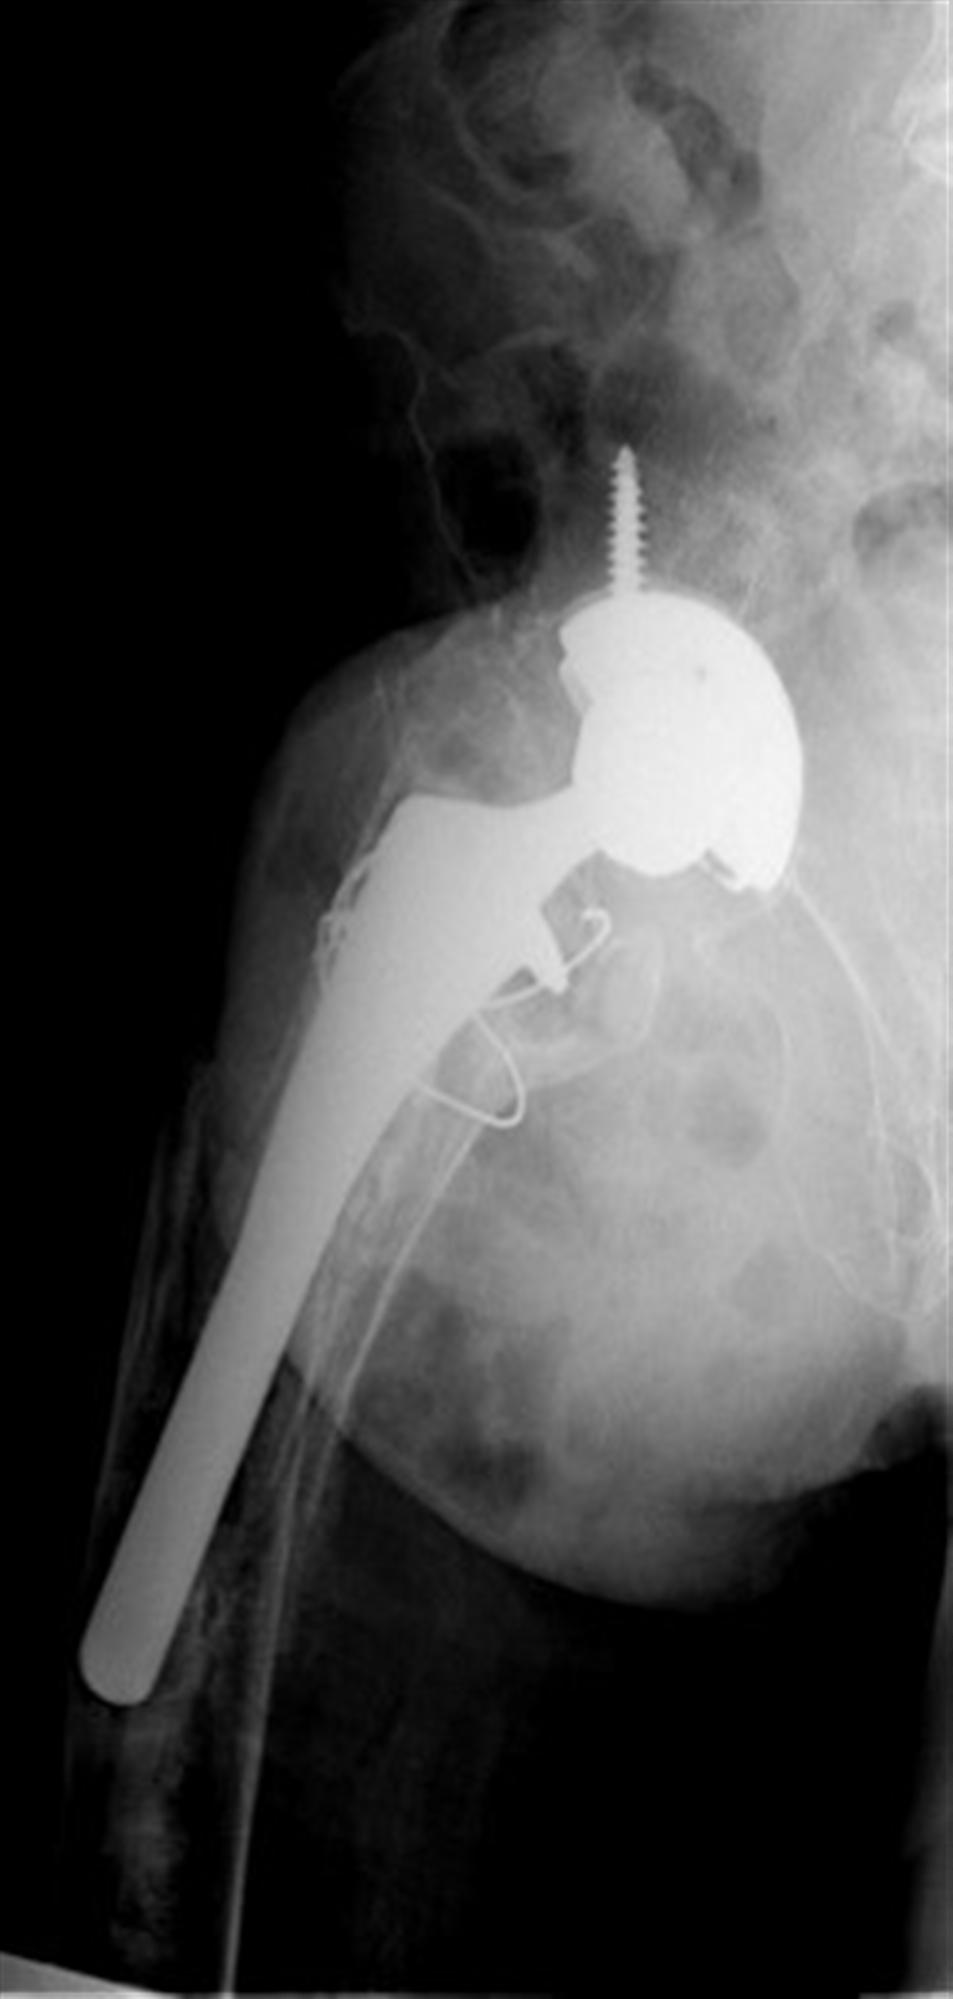

일상생활을 하다가 부러진 경우에도 똑같은 Vancouver Classification 을 사용합니다. 수술중과 큰 차이는 위치에 따라 골절을 나뉘고 B만 구체적으로 나누고 나머지는 그냥 A,C로 골절을 나뉩니다. STEM 이 헐거운 경우 B2, STEM 바로 아래는 B1, 삽입물 주변의 골절 또는 뼈가 부족한경우 B3로 이해하면 됩니다.